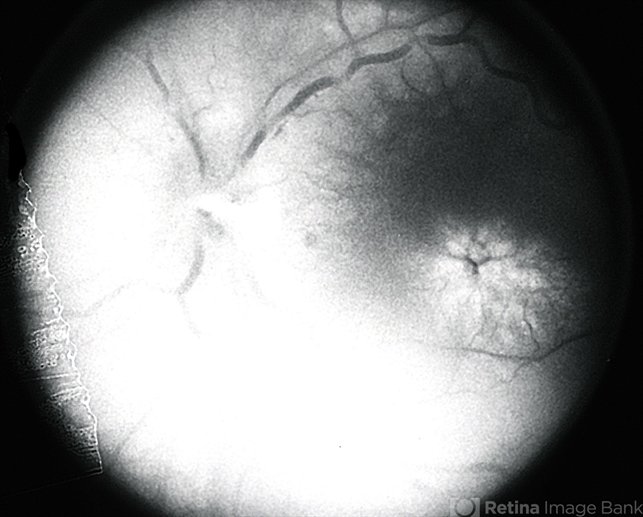

- cystoid macular edema (CME)

- Fluoroscein Angiogram with hot disc and CME.